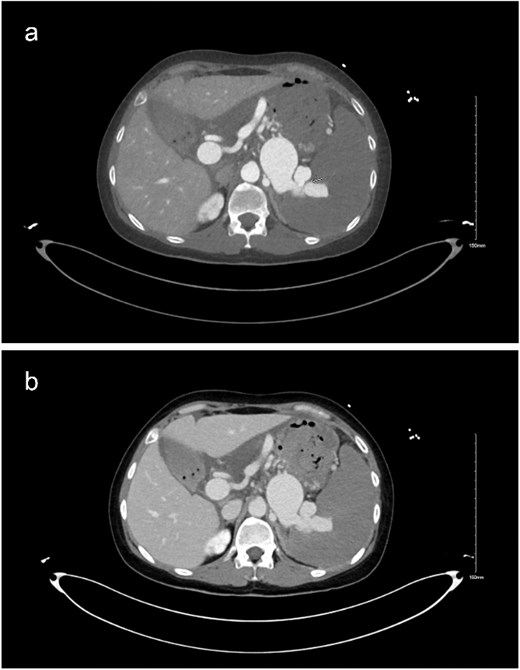

A computed tomography (CT) scan was obtained as part of the patient’s investigation plan, for which it revealed: no active bleeding. There was a distal SAA measuring 1.9 cm (Fig. 1c) with focal arteriovenous (AV) fistula with the distal splenic vein causing shunting of the flow with resultant severe aneurysmal dilatation of the splenic vein measures 3.4 × 9 × 4 cm (Fig. 1a–c). There were signs of portal hypertension seen as dilated portal vein measuring 2.8 cm (Fig. 2a and b) enlarged spleen measuring 20 cm. Other than that, the remaining of the CT was unremarkable.

(a and b) Delayed imaging CT of the abdomen and pelvis in axial view, showing the distended splenic vein and AV fistula at the hilum.